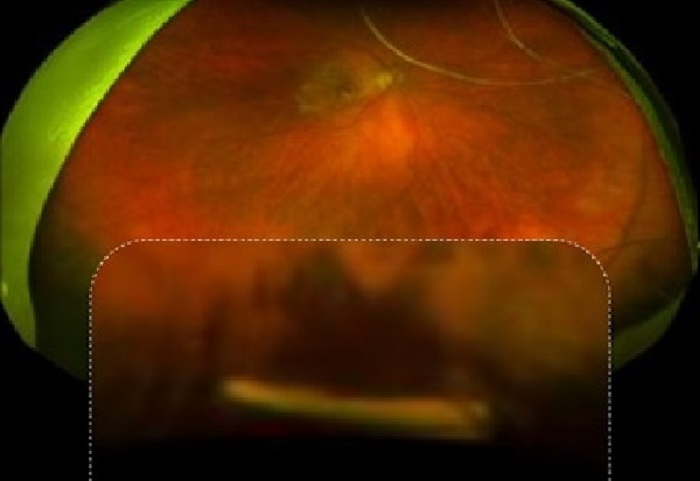

Figure 1: An implantable ophthalmic drug delivery device on a dime to show size.

In recent years, a novel, implant-based methodology has been in development for releasing anti-VEGF medication at a slow, steady rate over a long period of time (Figures 1 & 2). This technology is being developed both to extend the time between patient visits and to facilitate steady state medication release, which may help physicians control disease progression in a more even, predictable way.